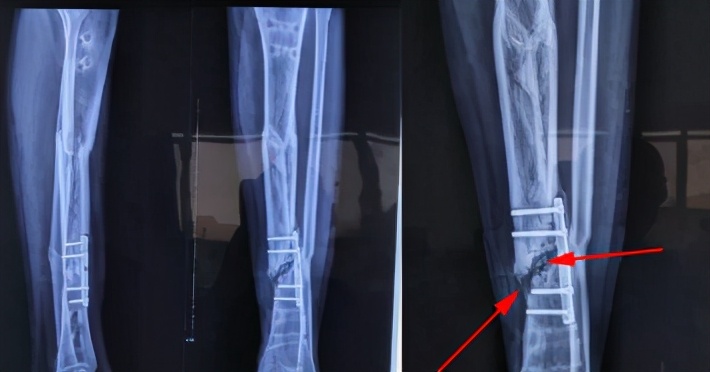

骨折断端局部血液供应情况:骨折部位有充足的血液供应被认为是最重要的因素之一。所以血供较差的部位如:腕舟骨,胫骨中下段,股骨颈等,骨折愈合较慢,很容易形成骨折不愈合。

断端稳定很重要:力学稳定是骨折正常愈合的重要条件。手术的目的除了复位骨折断端外,另一个重要作用就是维持断端稳定,为骨折愈合创造良好环境。

手术因素:手术中骨膜剥离过多,血运破坏多,软组织保护欠佳,断端间隙过大,固定后稳定性不够,均会影响骨折愈合。